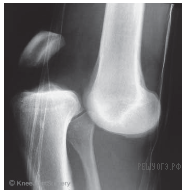

Как называют повреждение, изображенное на рентгеновском снимке?

1) гематома

2) перелом

3) вывих

4) ушиб

Ответ: